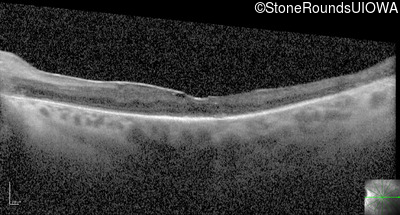

Optical Coherence Tomography - Left - 20/40 -1

Exemplar / OCT Stack

OCT Stack